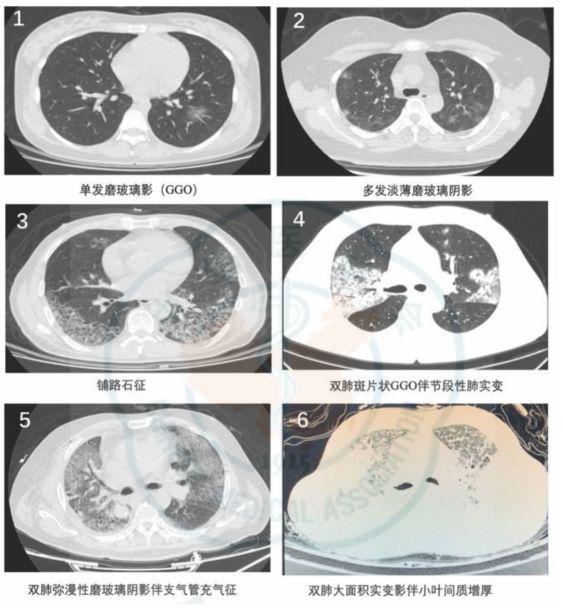

典型的新冠肺炎影像学并不难,诊断的关键是:

早期出现小斑片或间质性改变,常有磨玻璃阴影;

病灶主要位于胸膜下。随着病情进展,病灶常为双肺多发。

随着病情进展,CT失去特异性,不容易鉴别与一般的肺炎。

特别是后期变成“白肺”,没有之前的影像学做对比,更是没办法做出准确的诊断。